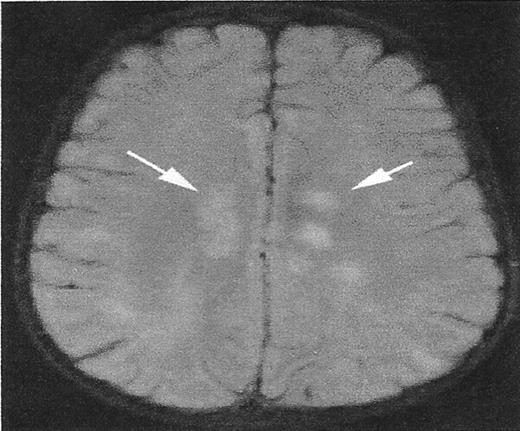

While the definition of the infarct-like lesion has been established, there are MRI signal abnormalities that mimic SCI but have distinct etiologies. Figure 1 illustrates this point. The T2 signal hyperintensities noted in the deep white matter are the result of acute disseminated encephalomyelitis, rather than SCA. However, the clinical setting would help distinguish these two entities. Other mimicry includes the sequelae of periventricular leukomalacia, dilated perivascular spaces, and delayed myelination in the terminal zones.

A lesion that mimics silent cerebral infarct (SCI).

High signal intensity lesions in the central white matter of both cerebral hemispheres (white arrows) in a child with acute disseminated encephalomyelitis. SCI often have a similar appearance.